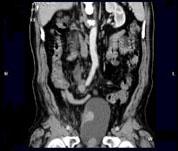

问题 男,73岁,无痛性全程血尿2个月余,CT检查如图所示,下列说法正确的是 ( )

选项 A、考虑为右侧输尿管中下段癌合并膀胱癌 B、考虑为右侧输尿管及膀胱结核 C、膀胱内可见宽基底的软组织肿块影 D、右肾及输尿管上段扩张积水 E、右输尿管中下段可见沿输尿管走行的长约10.6cm,不规则的软组织肿块影

答案 ACDE